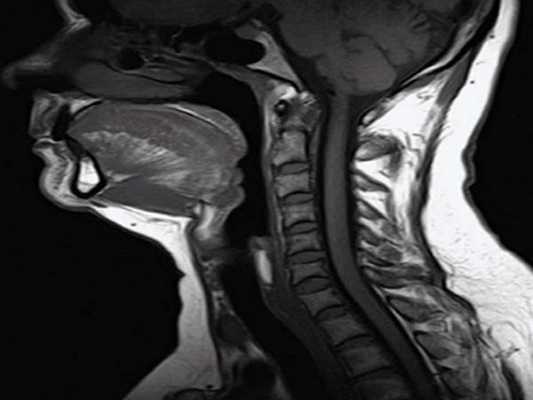

Ценность МРТ – превосходная детализация мягких тканей. МРТ превосходит КТ в качестве предпочтительного исследования при оценке ряда новообразований головы и шеи, таких как основание языка и слюнные железы. Размер, наличие нескольких увеличенных узлов и центральный некроз – критерии, общие для протоколов исследования КТ и МРТ.

Что показывает МРТ шеи

Магнитно-резонансная томография доказала свою эффективность в диагностике разных заболеваний. Это безопасный метод обследования, к нему прибегают специалисты разных профилей. Не исключение – МРТ мягких тканей шейного отдела.

На МРТ определяются структура и размеры всех органов и тканей, которые попадают в плоскость среза томографа. Плоскости и расстояние между срезами настраивает врач в зависимости от предполагаемой патологии.

- Опухоль хорошо накапливает контраст, выделяется среди нормальных тканей. Можно оценить ее величину, структуру, границы, из какой ткани растет, агрессивность по отношению к окружающим клеткам (вызывает их отек, разрушение или не затрагивает). На снимках видны как первичные опухоли, так и метастазы в регионарные лимфоузлы, соседние и отдаленные органы.

При оценке внутренних органов и лимфатических узлов в этой области можно определить размеры, форму, структуру. В норме она однородная, снимки могут выявить присутствие неоднородных включений (узлов, опухолей, камней, рубцов), сращение лимфоузлов между собой и с окружающими тканями.